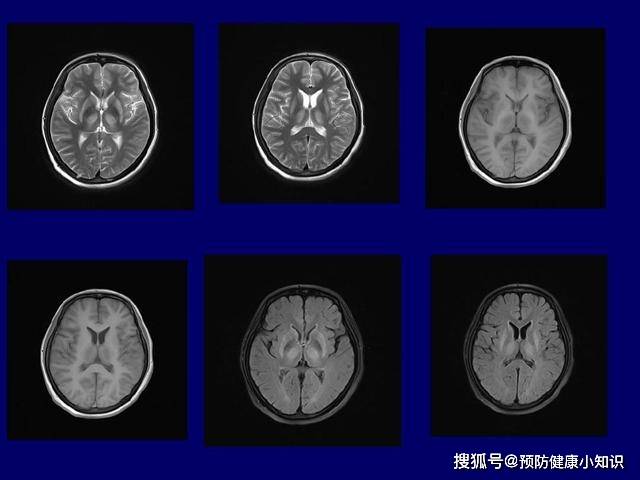

(2)神经症状

以表情古怪、肢体震颤、动作迟缓、肌肉强直、无意识的舞蹈、蠕动等为主要表现 。 有些病人还可能有语言障碍、平衡失调、步态不稳、癫痫等表现 。

文章图片